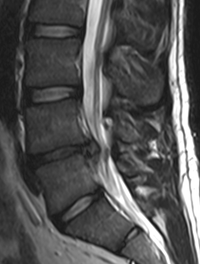

La radiculopathie lombaire aiguë, plus communément appelée sciatique, est en règle associée à une hernie discale du nucleus pulposus. [...]

La sténose rachidienne lombaire (LSS) est une altération anatomique caractérisée par un rétrécissement du canal rachidien et du foramen [...]

Le canal lombaire étroit est la première cause de chirurgie du rachis lombaire après 65 ans. La compression des structures neurologiques [...]

Le canal lombaire étroit est la première cause de chirurgie du rachis lombaire après 65 ans. La compression des structures neurologiques [...]